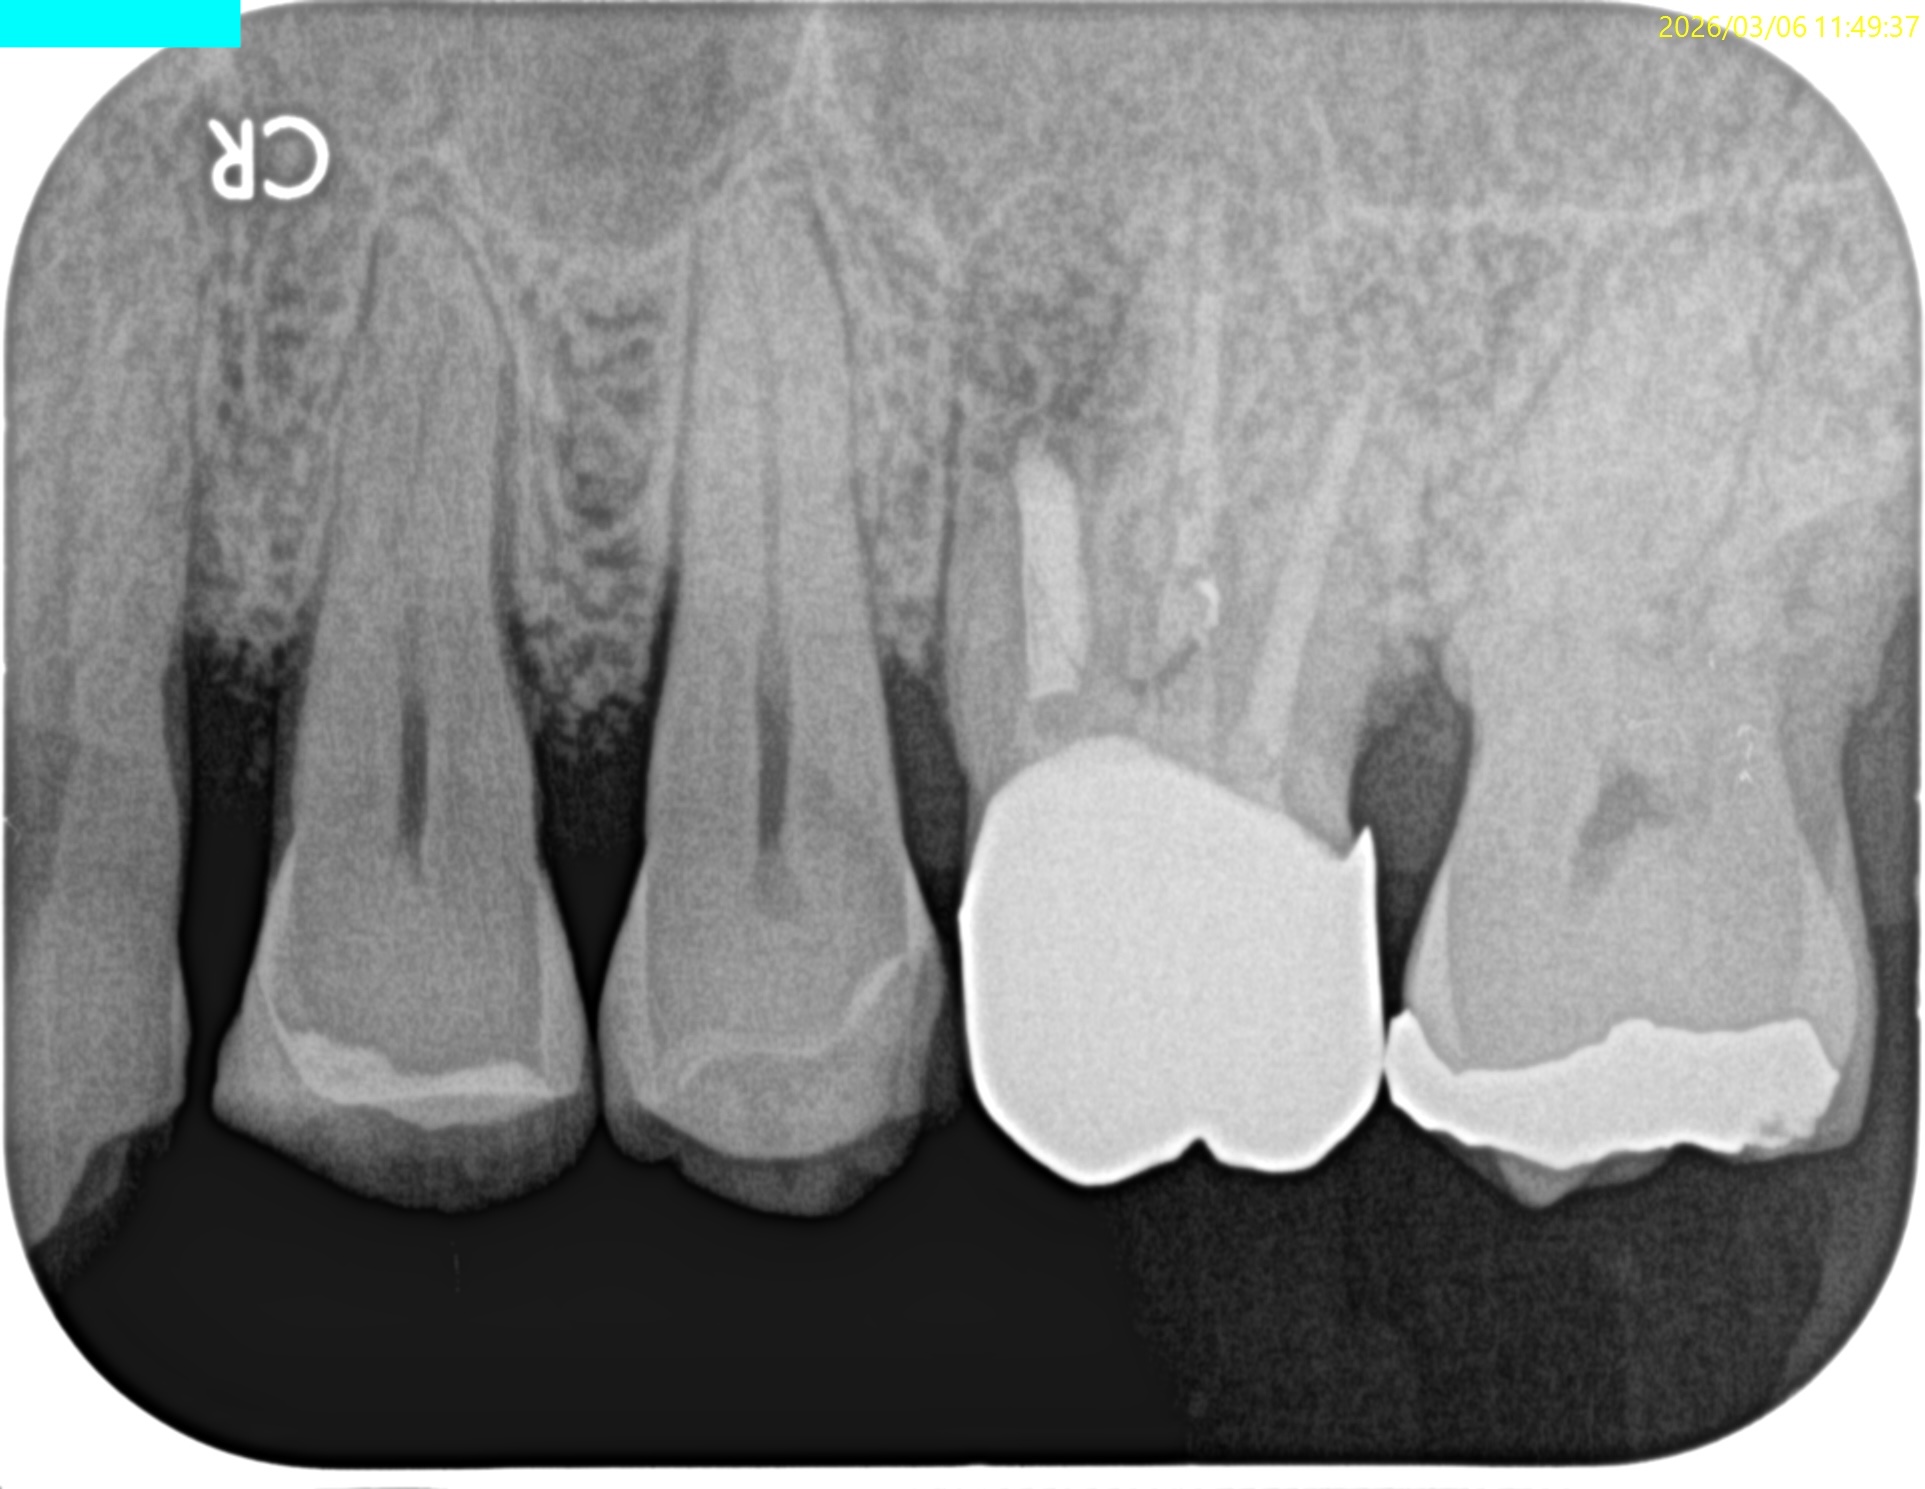

#14 MB Apicoectomy(2026.3.6)

MBの切断面が

このような形状になっていることから切断に問題がないことがわかる。

そしてこれをRetroprepすると、

このような状態になることが予想できる。

ということでRetroprepした。

PA, CBCTを撮影した。

逆根管充填材が頬側に寄っているような絵である。

が、だ。

これはこのような切断部位で観察していることになる。

いわゆる、

歯軸と並行でないのである。